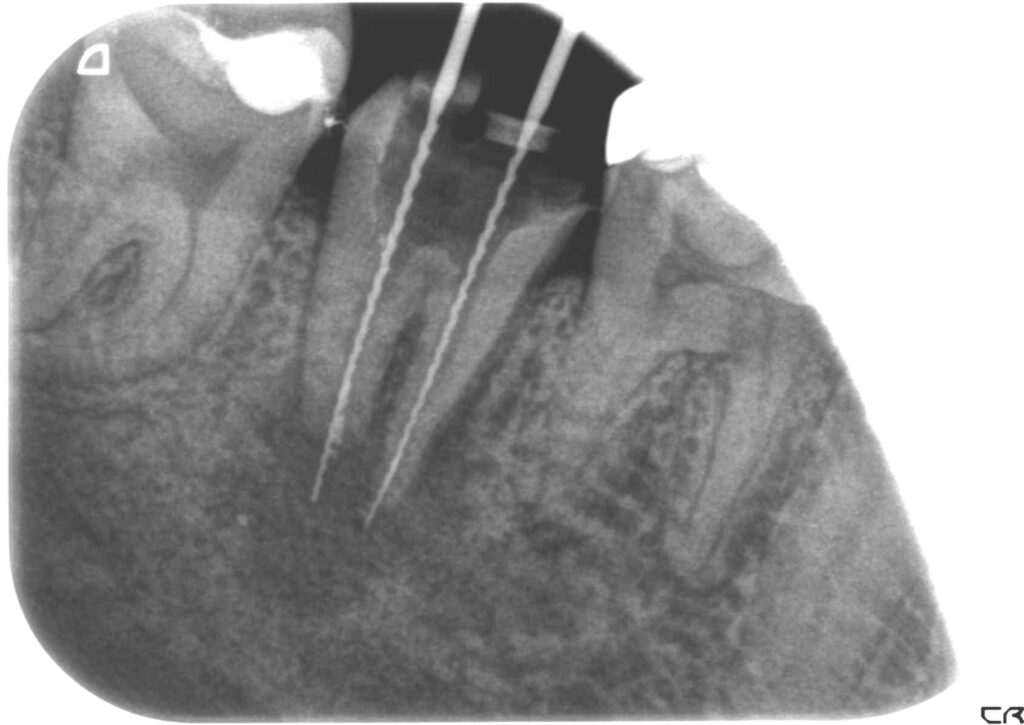

症例7

治療前

治療後

症例8根尖相当に広範囲に渡る大きな病巣

治療前

治療後

Before

外傷による打撲の為、神経が壊死し病巣が広範囲に拡がる

After

24ヶ月後 病巣もほぼ消失し、唇側骨板もしっかり再生されており、大変良い状態に回復している